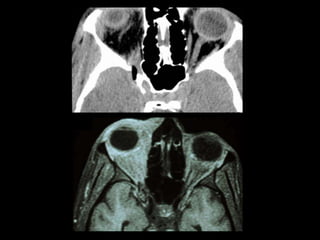

FRACTURA NASO-ÓRBITO-ETMOIDAL

(NOE)

• Golpe en nariz y transmisión posterior

etmoidal (contrafuertes maxilares mediales)

• Fractura del tercio medio facial que involucra

hueso etmoides (lámina perpendicular,

papirácea y cribiforme), propios nasales y

apófisis ascendentes de maxilares.

• Es la zona de la cara con menor resistencia a

fuerzas de fractura.

NOE

• Clasificación de Markowitz

– Tipo I: segmento central único, sin compromiso del

canto interno.

– Tipo II: segmento central conminuto, sin compromiso

del canto interno.

– Tipo III: segmento central conminuto, con

desinserción del canto interno.

FRACTURA NASO-ÓRBITO-ETMOIDAL (NOE) • Golpeen nariz y transmisión posterior etmoidal (contrafuertes maxilares mediales) • Fractura del tercio medio facial que involucra hueso etmoides (lámina perpendicular, papirácea y cribiforme), propios nasales y apófisis ascendentes de maxilares. • Es la zona de la cara con menor resistencia a fuerzas de fractura.

NOE • Clasificación deMarkowitz – Tipo I: segmento central único, sin compromiso del canto interno. – Tipo II: segmento central conminuto, sin compromiso del canto interno. – Tipo III: segmento central conminuto, con desinserción del canto interno.